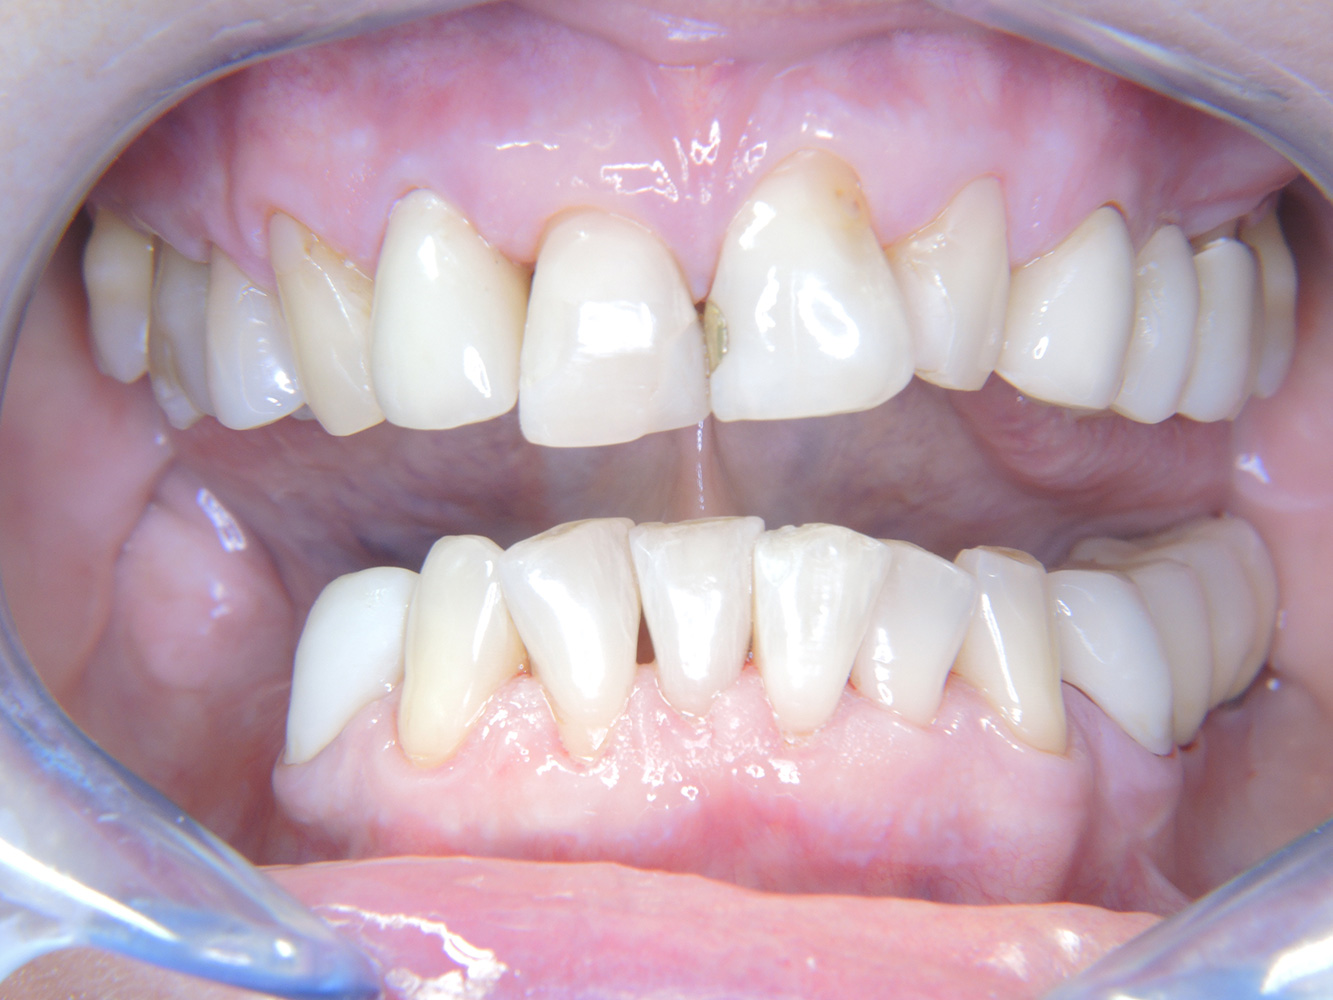

La paciente de 68 años no tiene enfermedades previas relevantes de la salud general ni toma medicación; sus hábitos alimentarios tampoco suponen un riesgo especial. La paciente tiene dos implantes (tercer cuadrante, desde hace cinco años) y una enfermedad previa periodontal (periodontitis en etapa IV, grado B) con pérdida dental. Actualmente las condiciones periodontales son estables, pero la periodontitis aumenta de manera determinante las complicaciones biológicas cuando se realizan implantes y puede ocasionar la pérdida de un implante (21). Para la sesión de profilaxis se hacen cuatro recomendaciones.

Dado que la paciente no tiene factores de riesgo especiales con efectos específicos para los dientes, las necesidades determinadas a partir de la salud oral son determinantes. Se recomienda un estado periodontal detallado una vez al año. De esta forma, es posible responder a la posible progresión de la enfermedad periodontal previa o al desarrollo de periimplantitis a tiempo.

Debido a la situación del implante con la enfermedad periodontal previa, la paciente tiene riesgo de desarrollar periimplantitis; se recomienda un intervalo de recuperación de tres a cuatro meses.